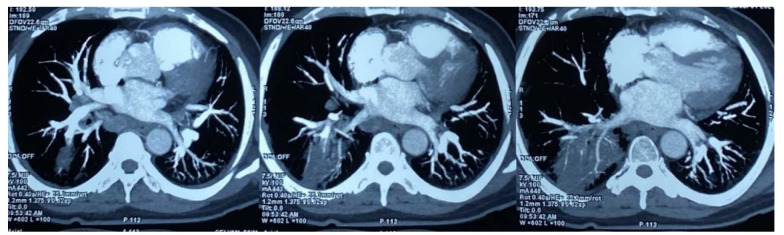

Results: Based on the findings, 8 (16%) out of 50 patients with rhino-orbital mucormycosis, had associated possible or probable pulmonary mucormycosis. All 8 patients were diabetics and had characteristic CT chest findings while only half of them had positive sputum microscopy. A higher prevalence of probably disseminated COVID-19-associated mucormycosis was noted among 51-60-year-old males with the use of corticosteroids and oxygen for COVID-19 therapy. The mortality rate was 100% in probably disseminated mucormycosis, 50% in possible disseminated mucormycosis, and only 9.5% in isolated rhino-orbital mucormycosis.

Abstract Image